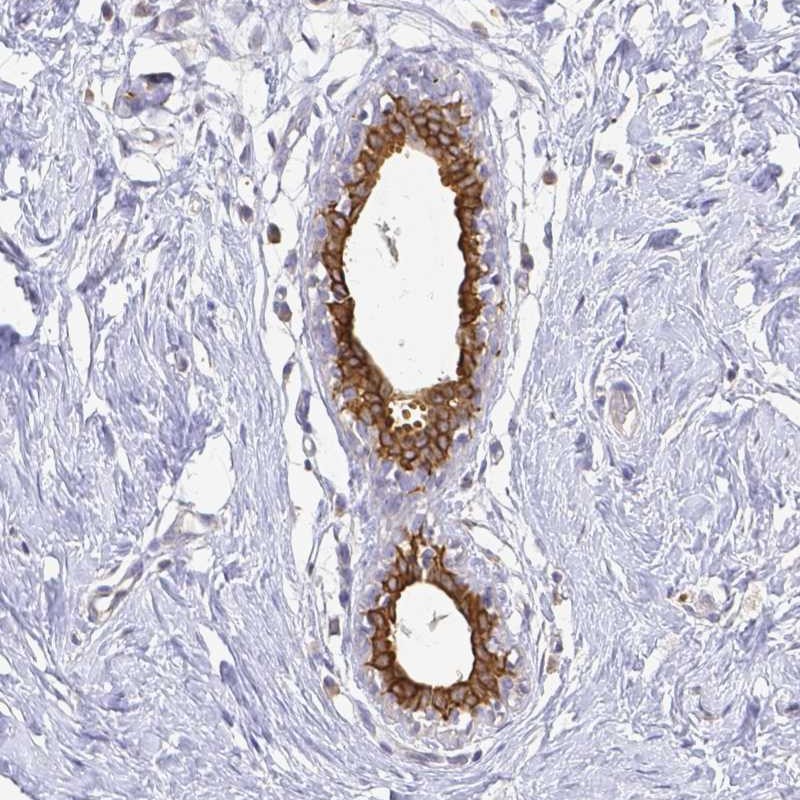

Immunohistochemical staining of human breast shows strong cytoplasmic and membranous positivity in glandular cells.